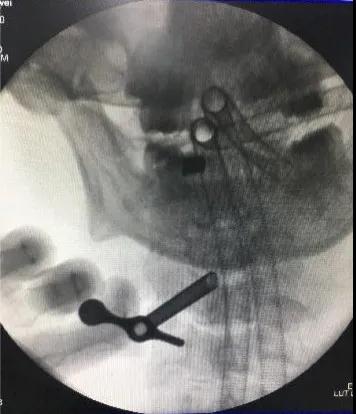

颈后路术后颈椎CT。

后入路术后见颈部椎管后方减压范围满意,骨性结构破坏小。

颈前路术后颈椎CT

前入路术后见颈椎间盘突出组织摘除完全。闫先生经住院治疗15天出院,治疗效果非常满意。